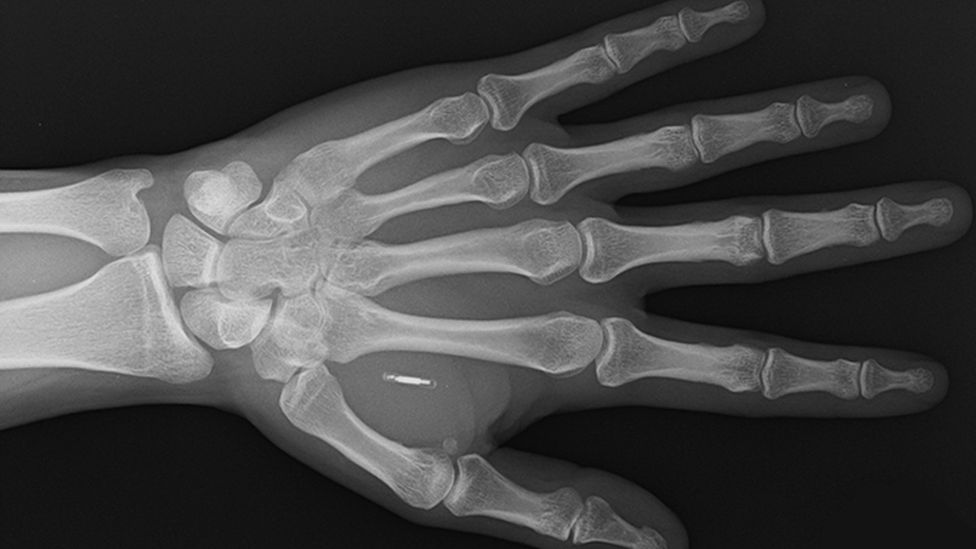

Ảnh chụp X-quang cho thấy mô cấy của Walletmor trong tay một người sau khi gây tê cục bộ |